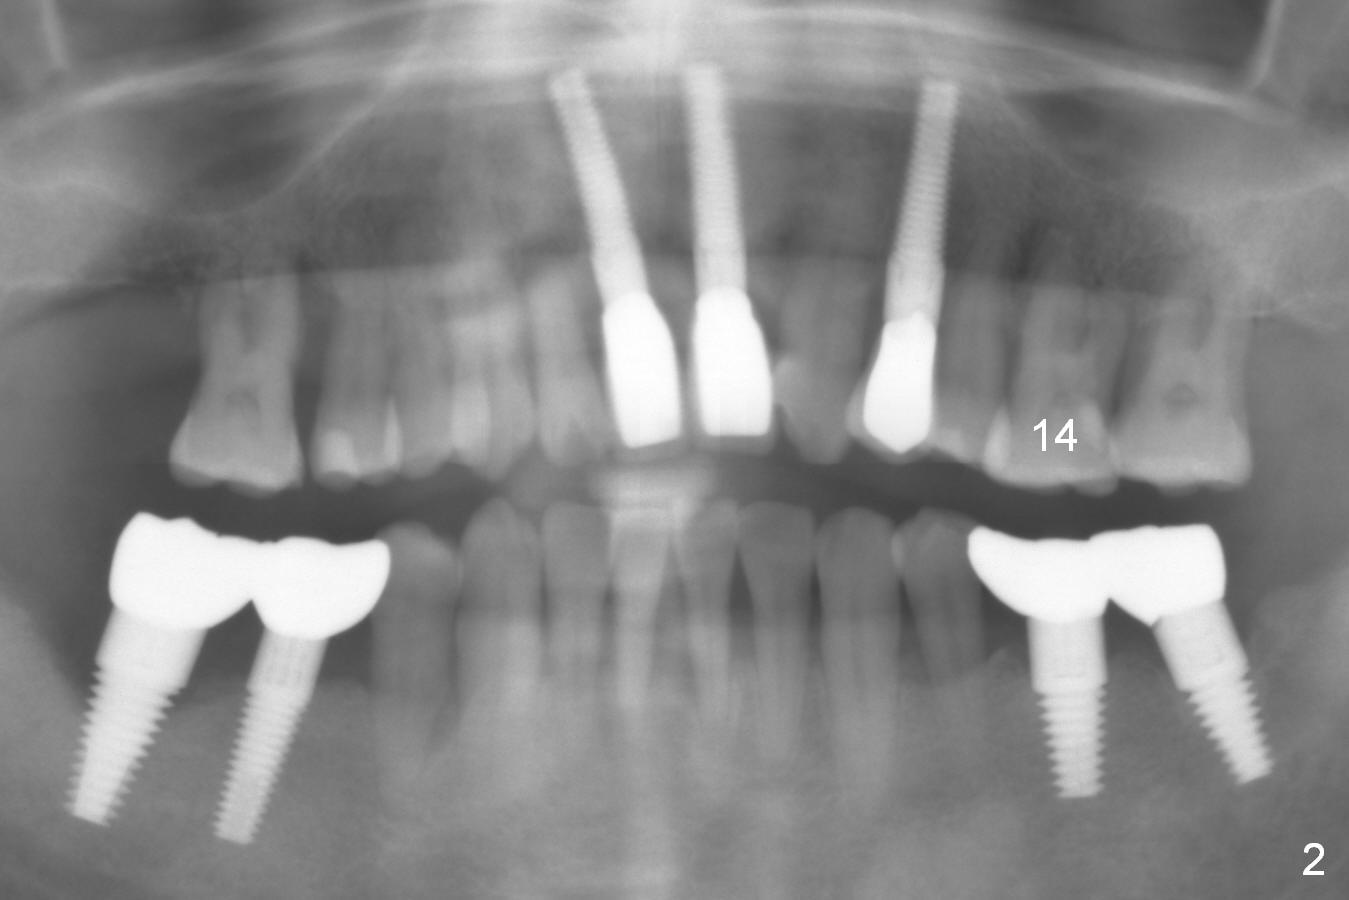

A 44-year-old man is a typical patient with chronic periodontitis (Fig.1).  Periimplantitis develops following immediate implant at #31 (Fig.2).  The symptom (bleeding) improves after bone graft and use of Water Pik.  Now the tooth #14 appears to be non-salvageable because of gingival hemorrhage and deep pockets after previous osseous surgery.  To prevent periimplantitis, an immediate implant does not need to be large or long.  It has to be placed deep, and in the middle of the native bone, surrounded by bone graft.  To facilitate wound healing, draw 3 tubes of blood for PRF.  One of them is processed for plug in case of sinus lift.  To prevent the buccal gingiva collapse, the buccal portion of the immediate provisional should extend into the socket.  If the gingiva is around 4 mm, use IBS implant (Fig.3,4).  Otherwise, a SM implant will be used after extraction (Clindamycin), since abutments have cuffs as long as 4.5 and 6 mm so that it is easy to place an implant as deep as possible.  Initial depth will be 9 mm (bone-level), followed by Magic Drill (5.3 mm, if possible) and Magic expanders (4.3x10 and 4.8x11 mm, bone density 26-300 units).